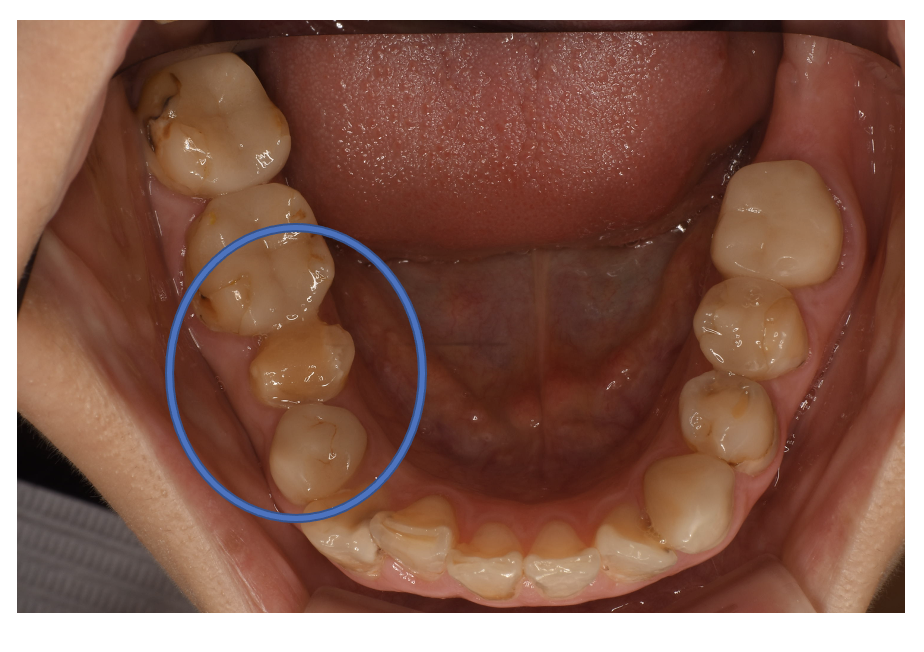

Before

| 備考 | 院長より プラスティック修復部の内部に虫歯が進行してしまっていたケースです。中を開けて見てみると、外から想像するよりもはるかに虫歯が広がってしまっていました。幸運にも神経を保存できたので、生きた臓器としてまだ使うことが可能です。残存歯質がかなり薄く弱くなってしまったので、ジルコニアで被せて守ってあげています。今回治療した歯の隣の歯、そして反対側の歯も当院で、フルジルコニアCrで被せている ケースです。これからも長く使っていけそうです。 |